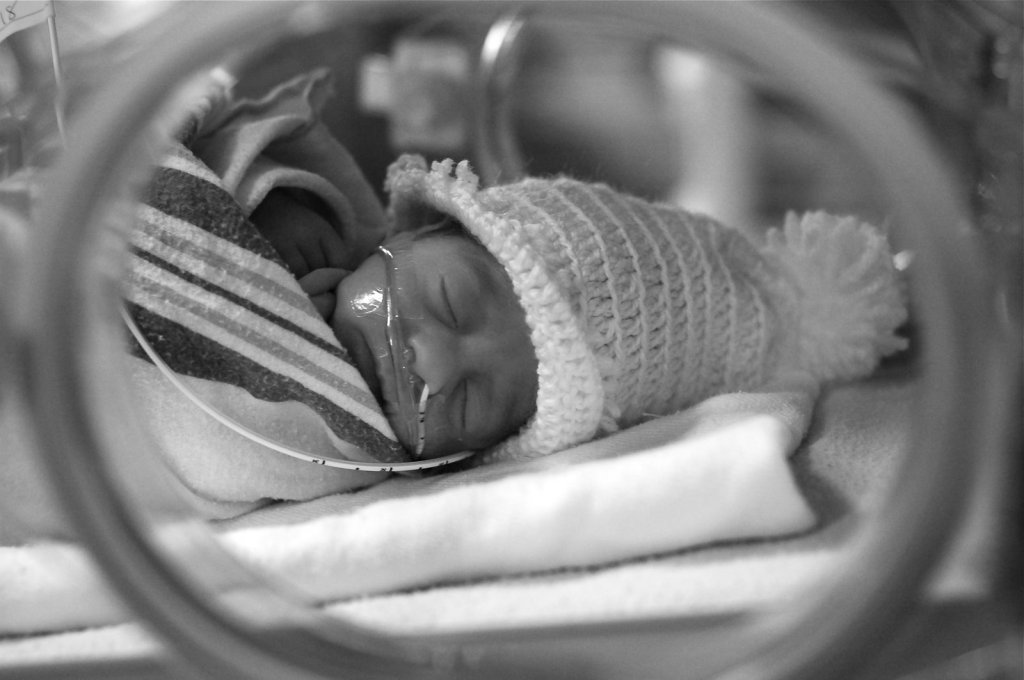

ชีวิตบนโลกใบนี้ของซูริค่อนข้างจะทรหดไม่แพ้กับในครรภ์ ด้วยน้ำหนักตัวที่ยังน้อย ปอดยังไม่พร้อมที่จะทำงาน ทำให้ต้องใช้ท่อช่วยหายใจ ระบบการกลืนยังไม่ทำงานจึงต้องใช้ท่อส่งอาหารลงกระเพาะ ภาพของการใส่ท่อทั้งสองในทารกขนาดประมาณฝ่ามือนั้นมันบาดตา ขนาดว่าคณะพยาบาลไม่เคยอนุญาติให้เราได้เห็นเลยแม้แต่ครั้งเดียว แน่นอนว่าดูน่ากลัวยิ่งกว่าภาพแรกที่เราได้โอกาสเข้ามาพบฝาแฝดทั้งสองในตู้อบที่เต็มไปด้วยสายระโยงระยาง เมื่อเรารู้ว่าลูกของเราทั้งสองจะไม่ได้กลับบ้านพร้อมกันกับเรา เราจึงหาที่พักใกล้โรงพยาบาลเพื่อที่จะได้อยู่กับพวกเชาทุก ๆ วัน เหมือนอย่างพ่อแม่มือใหม่คาดฝันไว้ก่อนคลอด

เราเฝ้ามองพัฒนาการของระบบต่าง ๆ ที่สำคัญ ของลูกทั้งสอง ขณะที่ทั้งสองดูมีพัฒนาการรวดเร็ว เซนสามารถออกจากตู้ได้แต่ซูริยังมีเรื่องของระบบการหายใจที่ดูเหมือนไม่พร้อมเสียที ซึ่งไม่ใช่ข่าวที่ดีมากนัก การใช้ท่อช่วยหายใจทำให้เกิดอาการข้างเคียงหลายอย่างตั้งแต่ระยะสั้น คือ ภาวะปอดติดเชื้อ ซึ่งทำให้มีไข้ ต้องให้ยาฆ่าเชื้อ และมีเสลดตามมา ซึ่งจะมีการไหลไปผิดที่ผิดทางจนต้องมีการดูดออก หรือผลข้างเคียงระยะยาวที่อาจจะทำให้ประสาทตาใช้งานไม่ได้ ทางแพทย์จึงมีความพยายามที่จะหยุดใช้ท่อหายใจให้เร็วที่สุดเท่าที่ทำได้ เพราะแม้ผลข้างเคียงระยะสั้นนั้นอาจจะลุกลามใหญ่โต การติดเชื้ออาจจะเข้าสู่กระแสเลือดทำให้เกิดอันตรายขึ้นได้ แต่ทุกครั้งที่มีความพยายามที่จะถอดท่อช่วยหายใจออก ซูริก็ยังไม่สามารถหายใจได้ด้วยตัวเอง เนื่องด้วยขนาดที่ค่อนข้างเล็กของซูริ อุปกรณ์ช่วยหายใจแบบที่เป็นหน้ากากครอบจมูกที่มีนั้นมีขนาดที่ใหญ่เกินไปไม่สามารถใช้กับซูริได้ต่างจากพี่เซนที่ใช้หน้ากากตัวนี้ช่วยในการฝึกหายใจวันช่วงวันสองวันแรก ซูริจึงจำเป็นต้องหายใจเองโดยไม่มีอุปกรณ์ช่วยเหลือ ซึ่งจะเกิดอาการตามมาคือ sleep apnea ที่ซูริจะลืมหายใจแล้วหลับไปเอง ต้องคอยมาสะกิดให้ตื่น อุปกรณ์เตียงแบบพิเศษที่คอยเคลื่อนไหวกระตุ้นไม่ให้เกิดอาการนี้ก็ได้พังไปหมดแล้ว อาการ sleep apnea จึงเป็นความเสี่ยงที่อันตรายมากกว่าความเสี่ยงจากการใส่ท่อช่วยหายใจ เนื่องจากเจ้าหน้าที่ที่มีจำกัด และความเสี่ยงของการปลุกไม่ตื่น นำไปสู่ภาวะฉุกเฉินที่ไม่มีเจ้าหน้าที่คนไหนต้องการให้เกิดขึ้นในกะของตน ซูริจึงต้องหายใจด้วยท่อช่วยหายใจเป็นส่วนมาก ต้องผ่านประสบการการใส่ท่อหลายต่อหลายครั้ง พบกับการติดเชื้อหลายครั้ง มีความจำเป็นต้องดูดเสลดเป็นประจำ และผ่านประสบการ sleep apnea เป็นครั้งคราว สภาวะนี้กับทารกที่มีอายุไม่กี่วัน น้ำหนักตัวเพียง 900 กรัม มันหนักหนาสาหัส มากพอควร มากกว่าความกังวลแรก ๆ ที่เราเคยกังวลกับ ปากแหว่งเพดานโหว่เล็ก ๆ นิ้วมือที่พัฒนาไม่ค่อยสมบูรณ์ หรือแม้กระทั่งความผิดปกติของโครโมโซมที่เรียกกันว่า triple X

เราอยู่กับเซนและซูริทุกวัน ตลอดเวลาที่เราตื่น จนในที่สุดเซนมีน้ำหนัก 1.8 กก. เมื่อเวลาผ่านไประมาณ 30 วัน และแพทย์ให้ออกจาก NICU เพื่อกลับบ้านได้ เซนก็จะอยู่กับเราตลอด 24 ชม. และก็มาใช้ชีวิตส่วนใหญ่ที่หน้าห้อง NICU ระหว่างที่เราเข้าไปเยี่ยมซูริ ซูริมีกำลังใจที่ดี ลืมตาขึ้นมาทักทายเราทุก ๆ ครั้ง แม้ว่าจะต้องสู้กับอาการไข้ ภาวะปอดติดเชื้อ หรือ ผ่านการดูเสมหะมาหมาด ๆ การรับอาหารก็ไม่มีปัญหาน้ำหนักตัวเพิ่มขึ้นเรื่อย ๆ จนเป็น 1.4 กก. จนในท้ายที่สุดคณะแพทย์มีความเห็นว่า ซูริควรที่จะหายใจเองได้แล้ว และเริ่มตั้งคำถามถึงสาเหตุว่าทำไม แล้วในเช้าวันหนึ่งคณะแพทย์จึงได้บอกกับเราว่า เขาต้องการส่องกล้องทางเดินหายใจเพื่อจะดูว่ามีอะไรผิดปกติหรือไม่ ผมเห็นดีด้วยเพราะผมเห็นความพยายามที่ไม่เป็นผลสำเร็จหลายต่อหลายครั้งในการที่จะถอดท่อช่วยหายใจ ซึ่งทำให้ต้องมีการใส่ท่อใหม่ที่สุดแสนจะทรมาน ผมเห็นความเจ็บป่วยที่เกิดจากการติดเชื้อ และการเจาะเส้นเลือดทั่วทั้งตัวรวมไปถึงบนศีรษะเพื่อที่จะให้ยาฆ่าเชื้อ ผมเองก็อยากรู้เช่นกันว่าทำไม ในวันถัดไปเราจึงนัดทำการส่องกล้อง แต่สิ่งหนึ่งที่ผมไม่เคยรู้มาก่อนเลยนั่นก็คือ ขั้นตอนนี้ต้องมีการให้ยาสลบ และการให้ยาสลบนั้นมีความเสี่ยงในตัวของมันเองอยู่ ในเช้าวันส่องกล้องแพทย์นำเอกสารที่ระบุถึงการรับรู้ถึงความเสี่ยงและแสดงความยินยอมให้ผมเซนต์ หลังจากนั้นผมจึงอุ้มซูริขึ้นมาจากตู้ ซูริหันมามองหน้าผมเช่นทุก ๆ ครั้งด้วยตากลมโต ยิ้มให้ผมที่มุมปากเล็ก ๆ ตามประสาการรับรู้ของพ่อที่มีต่อลูกน้อยที่มีอายุเพียง 49 วัน ก่อนที่ผมจะส่งให้กับคณะแพทย์ไป ส่วนผมเดินเข้าในนั่งรอในห้องพักแพทย์ภายในห้องผ่าตัด การผ่าตัดดำเนินไปได้ไม่นาน ก่อนที่ผมได้รับโทรศัพย์จากวิสัญญีแพทย์ที่เป็นรุ่นน้อง เรียกให้ผมเข้าไปด้านในห้องผ่าตัด เพื่อไปเห็นภาพซูริกำลังถูกปั้มหัวใจ แพทย์อธิบายว่าการส่องกล้องเป็นไปด้วยดี ซูริไม่มีอะไรผิดปกติที่ระบบทางเดินหายใจ แต่ซูริไม่ยอมตื่นจากยาสลบ